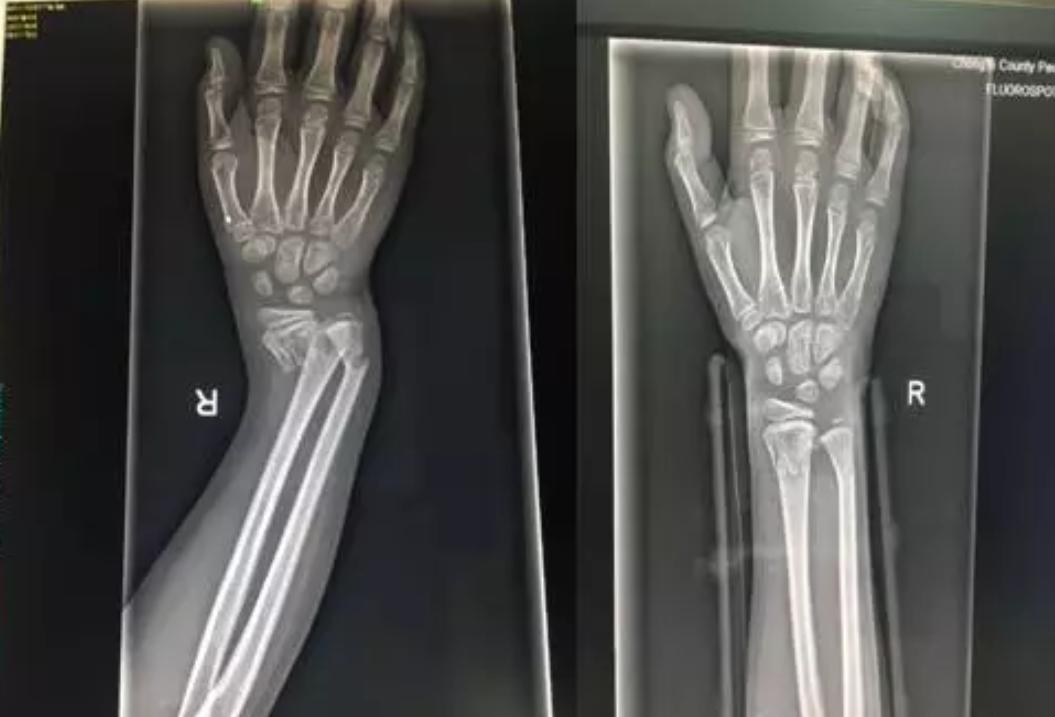

由上图能够看出孩子的右手腕明显的畸形

DR片提示右桡尺骨远端骨折。因为骨折严重错位,孩子疼痛的已经脸色惨白,我们将治疗方式提供给患儿家属,征得同意后实施正骨手法复位。准备好一切所需要的物品,如绷带、夹板、扎带、棉垫、压垫。孩子很坚强,积极配合,吴医生与朱医生默契配合,在场的人都屏住呼吸,希望医生能够一次复位告捷,避免孩子再承受更多的痛苦。牵引、复位一气呵成。

在场的人都松了一口气,固定夹板,交待注意事项,复查。让我们看看复查前、后的DR片吧!